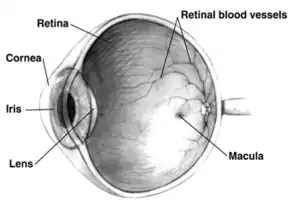

Right human eye cross-sectional view; eyes vary significantly among animals. | |

The retina (from Latin rete 'net'; pl. retinae or retinas) is the innermost, light-sensitive layer of tissue of the eye of most vertebrates and some molluscs. The optics of the eye create a focused two-dimensional image of the visual world on the retina, which then processes that image within the retina and sends nerve impulses along the optic nerve to the visual cortex to create visual perception. The retina serves a function which is in many ways analogous to that of the film or image sensor in a camera.

In adult humans, the entire retina is about 72% of a sphere about 22 mm in diameter. The entire retina contains about 7 million cones and 75 to 150 million rods. The optic disc, a part of the retina sometimes called "the blind spot" because it lacks photoreceptors, is located at the optic papilla, where the optic-nerve fibres leave the eye. It appears as an oval white area of 3 mm2. Temporal (in the direction of the temples) to this disc is the macula, at whose centre is the fovea, a pit that is responsible for sharp central vision, but is actually less sensitive to light because of its lack of rods. Human and non-human primates possess one fovea, as opposed to certain bird species, such as hawks, that are bifoviate, and dogs and cats, that possess no fovea, but a central band known as the visual streak. Around the fovea extends the central retina for about 6 mm and then the peripheral retina. The farthest edge of the retina is defined by the ora serrata. The distance from one ora to the other (or macula), the most sensitive area along the horizontal meridian, is about 32 mm.